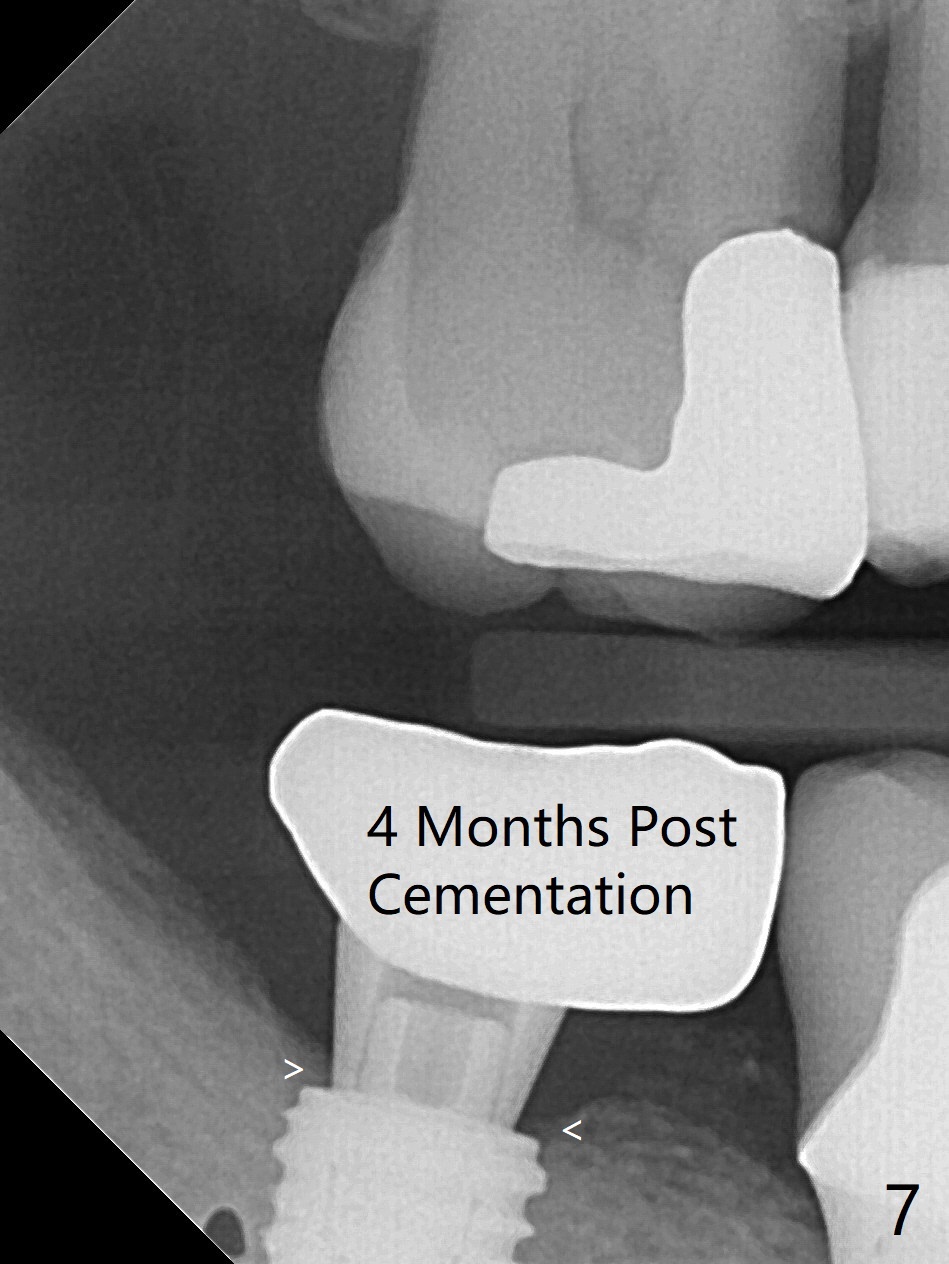

61岁女右下7导板钻洞,第一个钻头(环形钻)就有困难入位,部分磨去对合7近中腭侧牙尖(图一:*),钻头入位就好多了(图二:^,对比)。钻洞时发现骨质密度中等,所以最后钻头直径4.5毫米。不过无法用手植牙工具旋入植体,使用5.0毫米功螺纹钻头后,手工具就好用了,植体植入一定深度,扳手有空间插入,最后扭力30Ncm。第二个问题,当按照设计深度植入植体,用探针检查颊侧好像没有骨壁;加深大约0.5毫米(仿佛没有取到目的,颊侧骨板不明显)后,使用6毫米profile钻头,插入5.5x3毫米愈合基台(图二,三),在基台和颊侧牙龈之间植入异体骨粉,但愿帮助颊侧骨板再生。术后一周内敷料脱落,颊侧伤口愈合,好像骨粉没有流失。术后2.5月愈合基台脱落,换至小号基台(4向毫米),仍旧疼痛,休息2分钟,手拧紧,拍摄根尖片,仿佛就位(图四)。准备一周后调换稍微大,例如,4.8毫米基台。术后3.5个月,5.2毫米基台好像没有就位(图五:<),可能与远中牙槽嵴接触(*)。小一号基台仿佛就位(图六),与远中牙槽嵴无接触。术后4个月粘固后基台螺丝拧紧30Ncm。术后8个月,也就是粘固后4个月,牙槽嵴似乎试图覆盖植体平台(图七:箭头)。